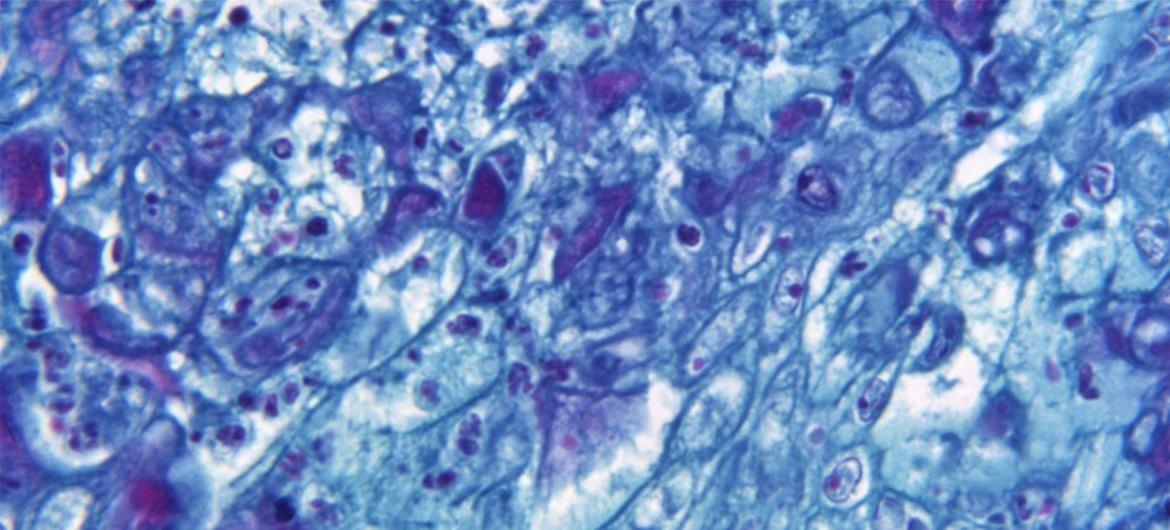

El virus de la viruela del mono se transmite con mayor frecuencia a través del contacto directo con la erupción o las llagas de alguien que tiene el virus. También puede propagarse a través del contacto con la ropa, la ropa de cama y otros artículos utilizados por una persona con la enfermedad, o por las gotitas respiratorias que pueden transmitirse a través del contacto prolongado cara a cara. Aún no se conoce del todo el riesgo de transmisión por aerosol. La OMS recomienda que el personal sanitario que atiende a los pacientes con viruela del mono lleve una mascarilla.

Los síntomas suelen comenzar entre siete y 14 días después de la exposición, pero en algunos casos pueden no aparecer hasta los 21 días. El síntoma más común es una erupción o llagas en la piel. También pueden aparecer síntomas similares a los de la gripe, como fiebre, ganglios linfáticos inflamados, dolor de cabeza y cansancio. En algunos casos, la viruela del mono puede causar una enfermedad grave.